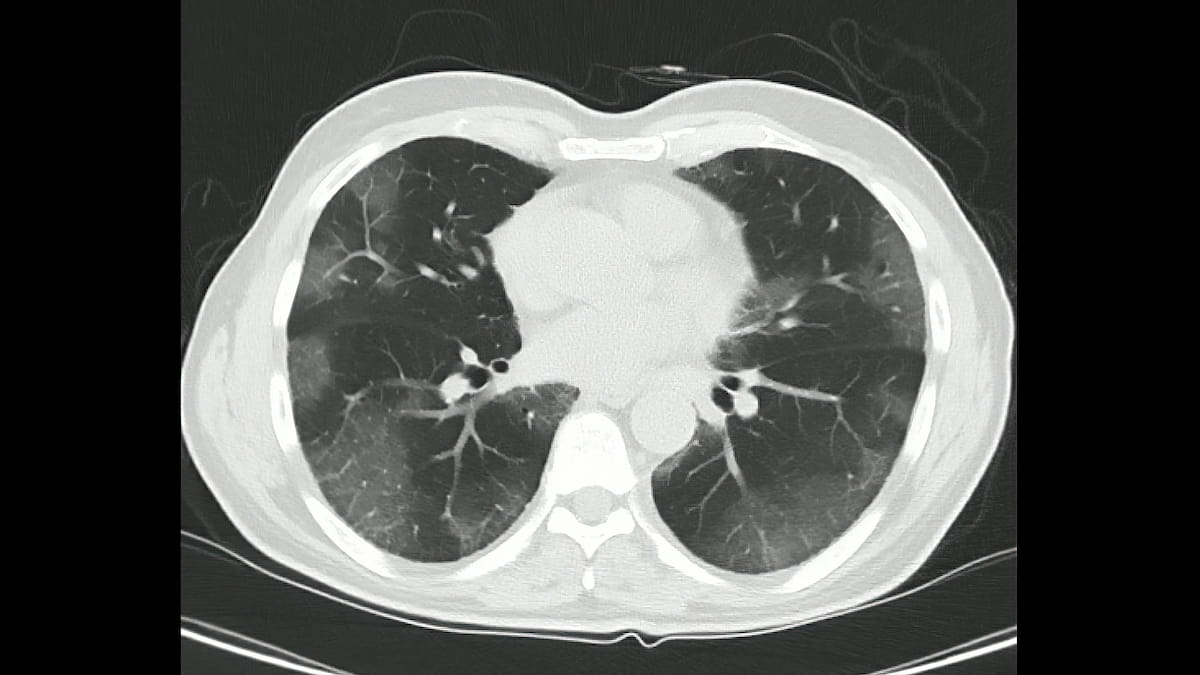

Data Backs CT Lung Screening in More High-Risk Patients

NCCN Group 2 high-risk patients to benefit from CT lung screening, study says.

A retrospective review of an additional group of patients at high-risk for lung cancer - or National Comprehensive Cancer Network Group 2 patients - showed that annual lung screening had similar rates of positivity and lung cancer diagnoses in these patients as those seen in patients in the National Lung Screening Trial (NLST).

Based on results of the NLST, annual CT screening is currently recommended in patients aged 55 to 74 with a 30 pack-year or greater smoking history or current or former smokers who quit within the past 15 years. The NCCN Group 2 is patients aged 50 or older with a greater than 20 pack-year smoking history, current or former smokers who quit for any length of time, and those with at least one additional lung cancer risk factor, excluding second hand smoke exposure.

Results of the imaging examination showed positive results, clinically significant incidental findings, and suspected pulmonary infection in 25%, 6%, and 6% of patients in group 2 and 28.2%, 6.2% and 6.6% in group 1, respectively.